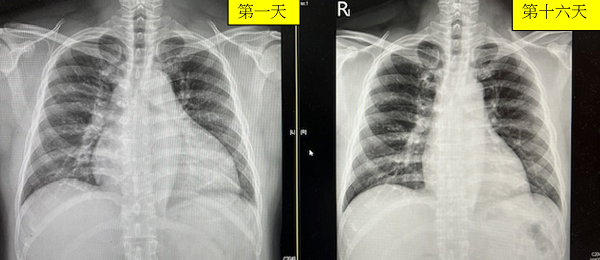

臺北市立聯合醫院陽明院區心臟內科主任曾梓維表示,最近半年之中就有兩位年約40至50歲的男子,長期三高不控制因此心臟衰竭造成呼吸困難、無法平躺睡以及全身水腫的病人來到門診及住院治療,經藥物治療後,不只心衰竭症狀改善,心臟擴大在16天之內回復正常大小,心臟收縮力(LVEF,left ventricular ejection fraction)也由使用藥物前的28%上升到48%的案例。可見近代心衰藥物及治療確實有了長足進步。

胸部X光照片(圖片來源:曾梓維醫師提供)